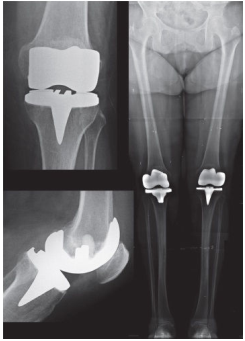

Observe as seguintes radiografias simples, sendo todas do mesmo paciente.

Diante do exposto, é correto afirmar que a paciente foi submetida a uma